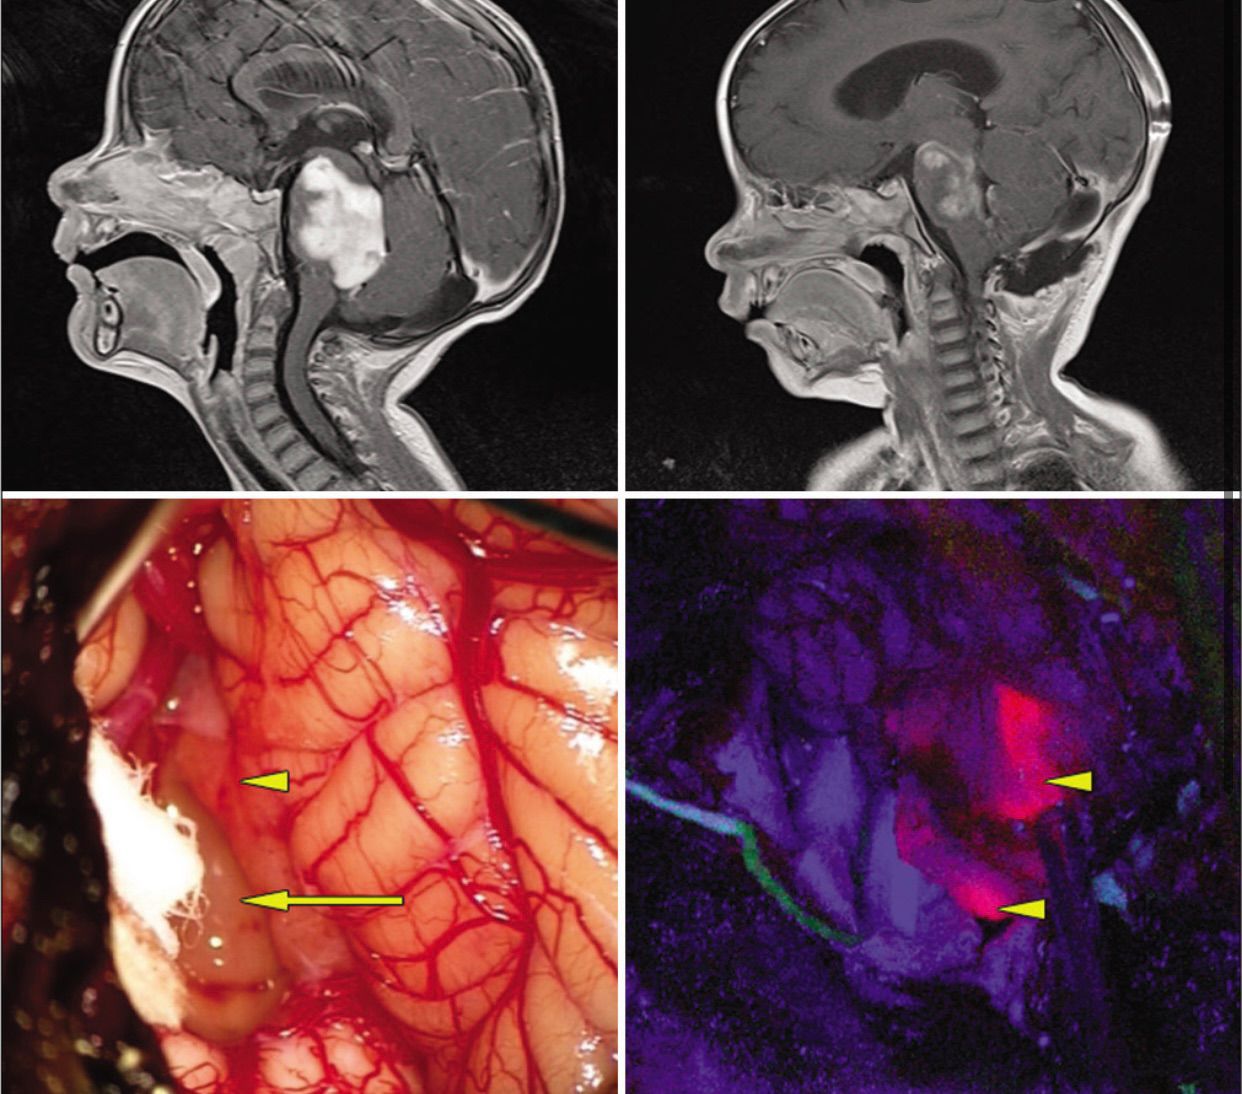

With infiltrative high grade gliomas, such as WHO grade IV intra-axial brain tumors (glioblastoma multiforme), neoplastic cells attach to nearby brain that cannot be visualized by MRI or neuronaviagtion. 5ALA is a compound that is given to patients who are undergoing a craniotomy procedure for the resection of malignant brain tumors. This compound will get metabolized by the neoplastic cells and a neurosurgeon can use 410 nm light from the operative microscope to be more aggressive with the extent of resection. As usual, if diagnosed to be GBM, chemotherapies include temozolomide and bevacizumab and radiosurgery is an option for treatment. However, Temodar does not work for a margin of patients if they have an unmethylated mgmt promoter.